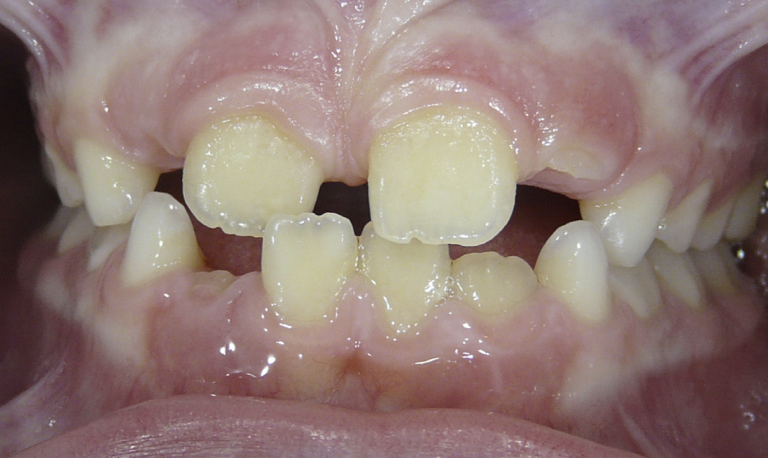

Openbite

Front teeth do not meet when teeth are closed.